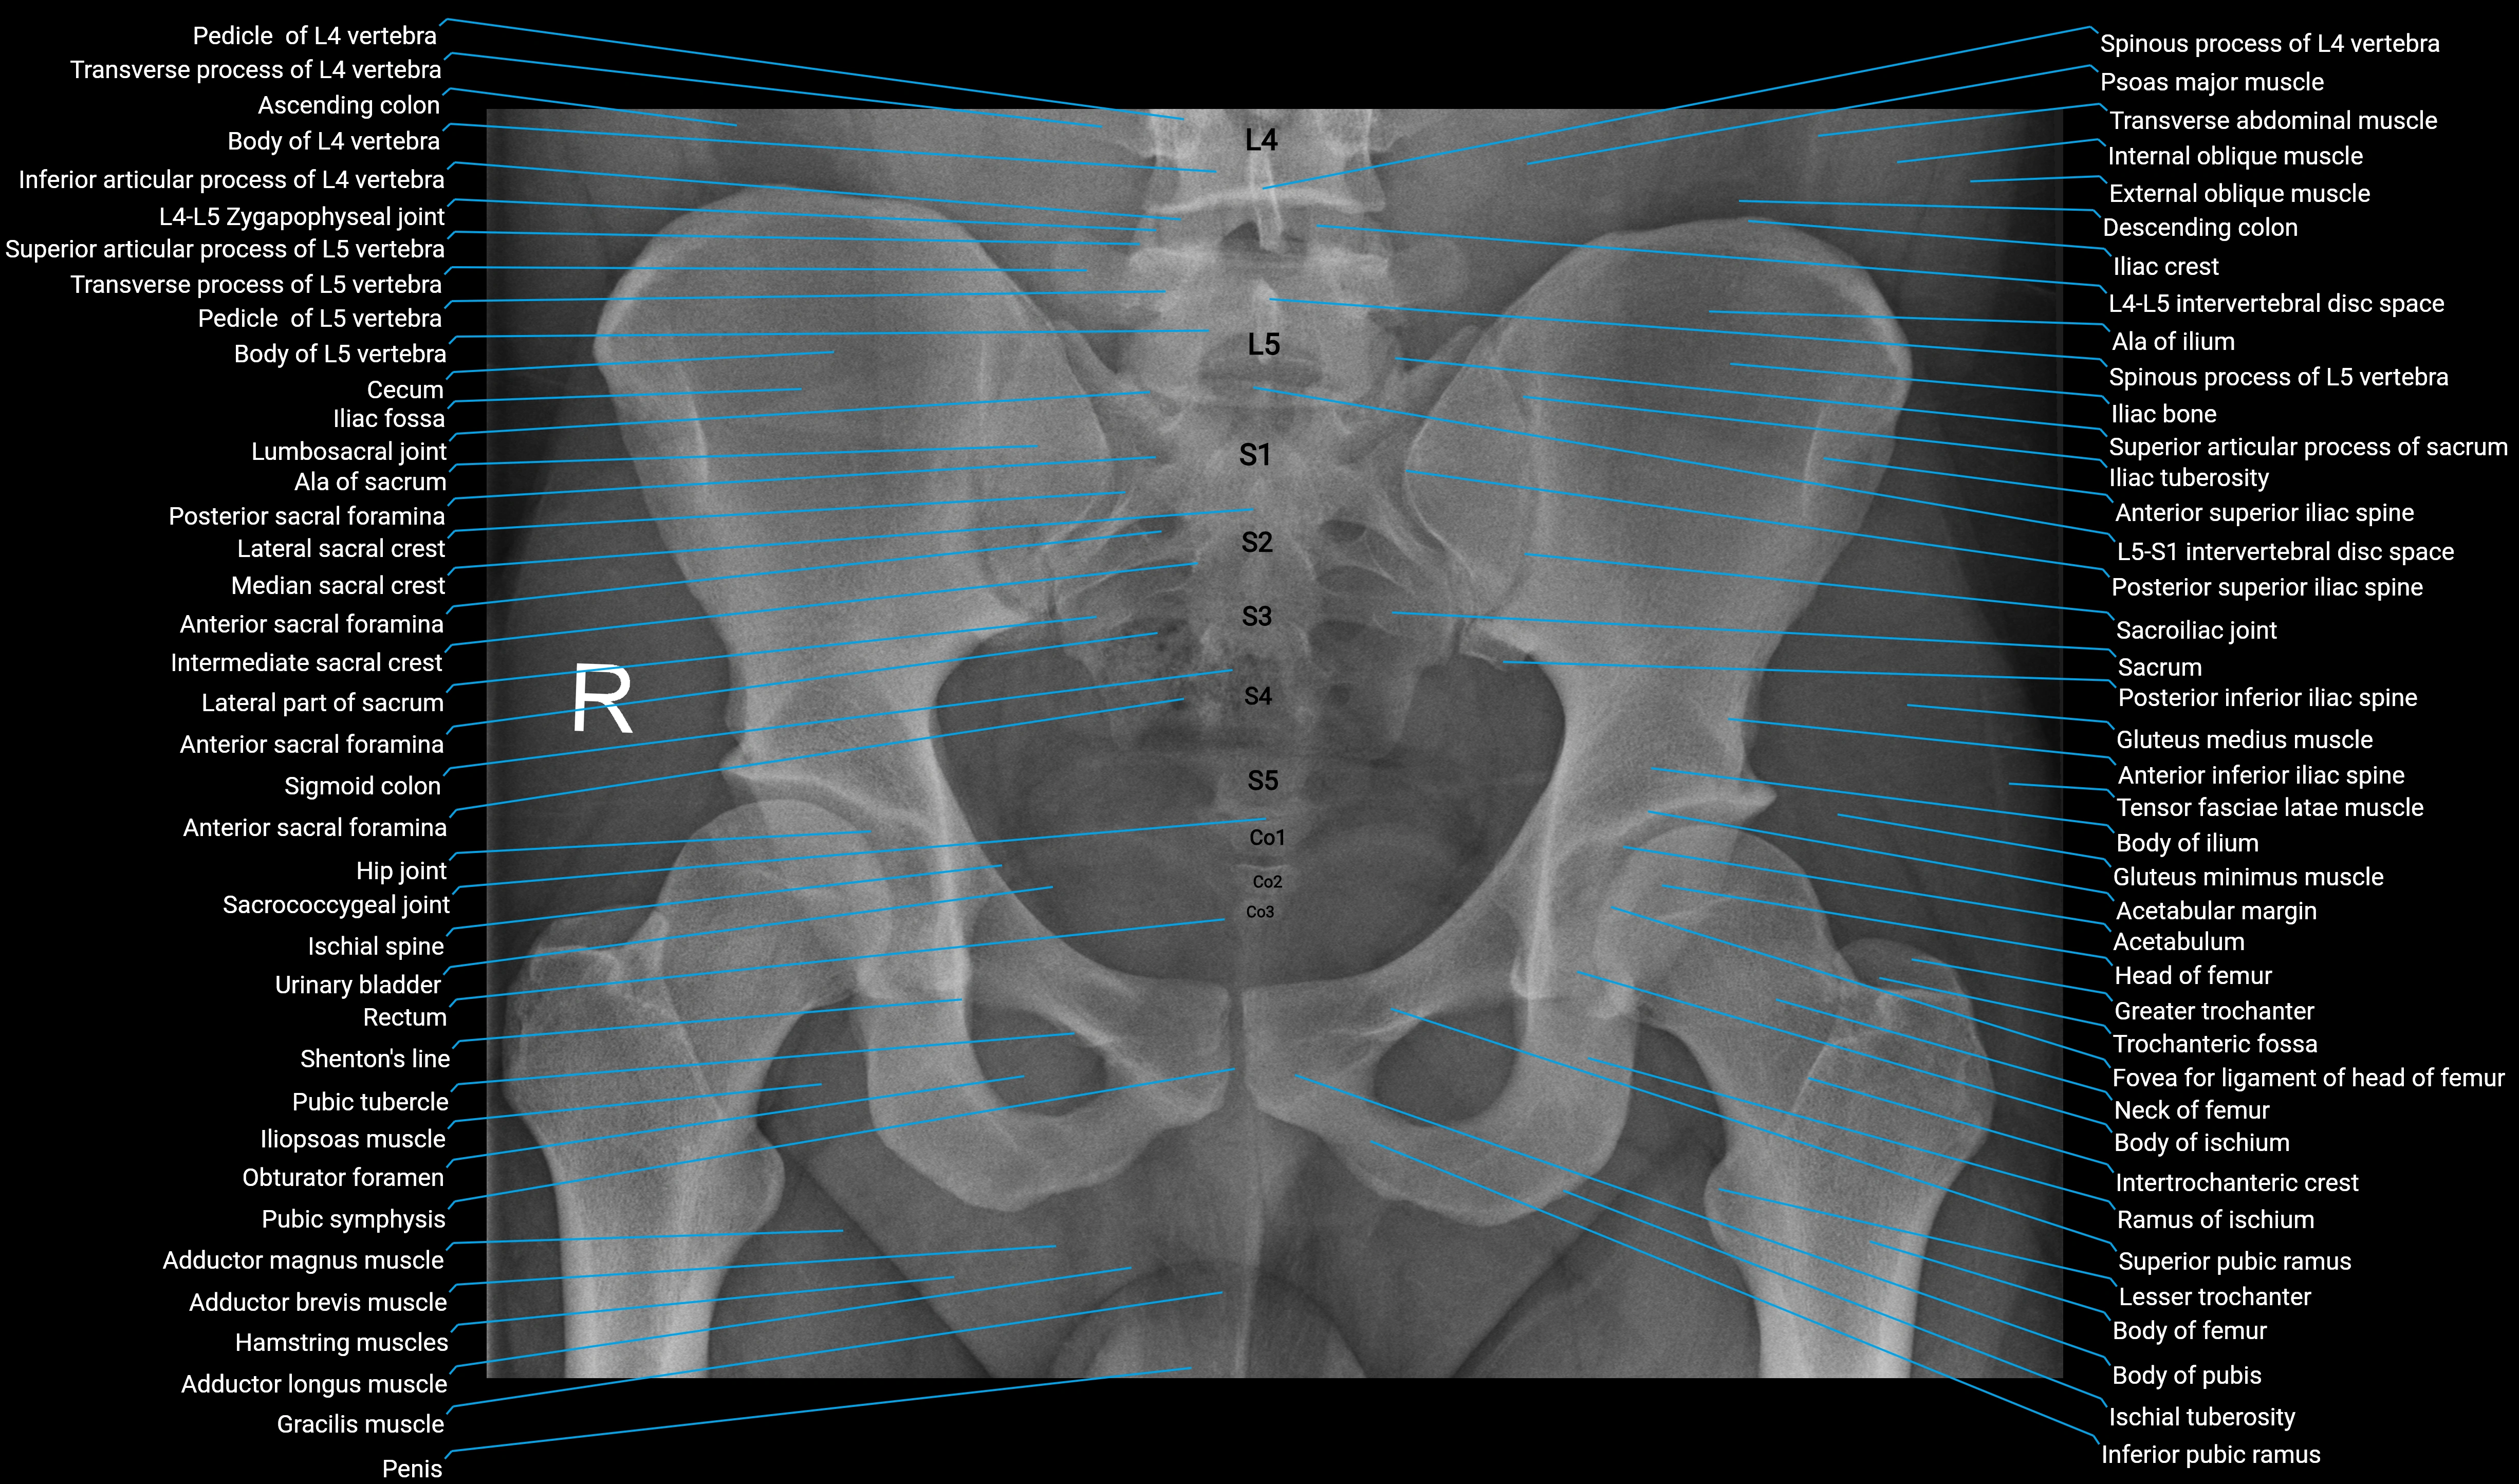

- Acetabular margin (Acetabular rim)

- Acetabulum

- Adductor brevis muscle

- Adductor longus muscle

- Adductor magnus muscle

- Ala of ilium (wing of ilium)

- Ala of sacrum

- Anterior inferior iliac spine

- Anterior sacral foramina

- Anterior superior iliac spine

- Ascending colon

- Body of femur

- Body of ilium

- Body of ischium

- Body of pubis

- Cecum

- Descending colon

- External oblique muscle

- Fovea for ligament of head of femur

- Gluteus medius muscle

- Gluteus minimus muscle

- Gracilis muscle

- Greater trochanter

- Hamstring muscles

- Head of femur

- Hip joint

- Iliac bone

- Iliac crest

- Iliac fossa

- Iliac tuberosity

- Iliopsoas muscle

- Inferior articular process of vertebra

- Inferior pubic ramus

- Intermediate sacral crest

- Internal oblique muscle

- Intertrochanteric crest

- Ischial spine

- Ischial tuberosity

- L (Lumbar spine)

- Lateral part of sacrum

- Lateral sacral crest

- Lesser trochanter

- Lumbosacral joint

- Median sacral crest

- Neck of femur

- Obturator foramen

- Penis

- Posterior inferior iliac spine

- Posterior sacral foramina

- Posterior superior iliac spine

- Psoas major muscle

- Pubic symphysis

- Pubic tubercle

- Ramus of ischium

- Rectum

- S (Sacral spine)

- Sacrococcygeal joint

- Sacroiliac joint

- Sacrum

- Shenton’s line

- Sigmoid colon

- Small intestine

- Spinous process of vertebra

- Superior articular process of sacrum

- Superior pubic ramus

- Tensor fasciae latae muscle

- Transverse abdominal muscle

- Transverse process of vertebra

- Trochanteric fossa